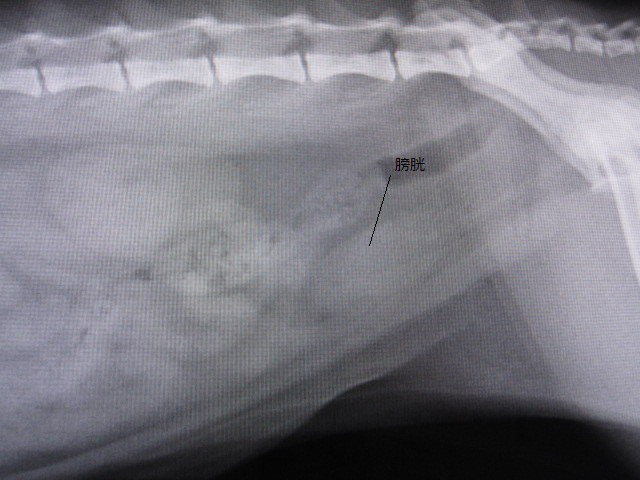

術後

術後のレントゲンです。

結石はなくなりました。